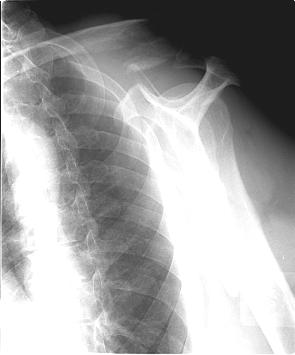

There were some cases of lateral clavicle fractures but right now i have available only images of pure acj cases. The frame is the same as i would assembly for the discussed injury. See attachment.

Biomechanics of the injury requires the same ex-fix approach as for ACJ dislocation. So a lateral reference wire is placed into the acromion.